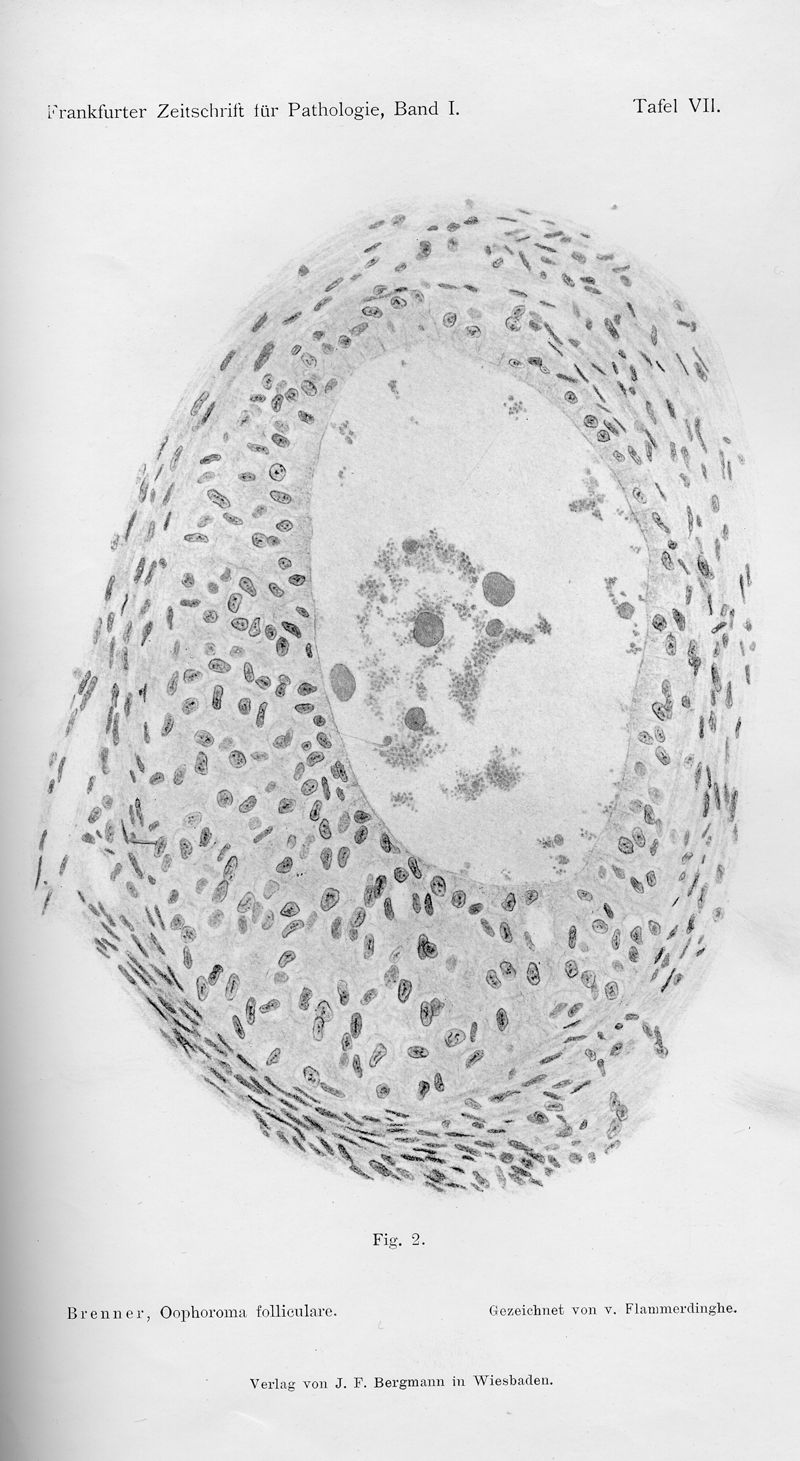

In : Frankfurter Zeitschrift für Pathologie,

1907, vol. 1, pp. 150-71

In : Frankfurter Zeitschrift für Pathologie,

1907, vol. 1, pp. 150-71